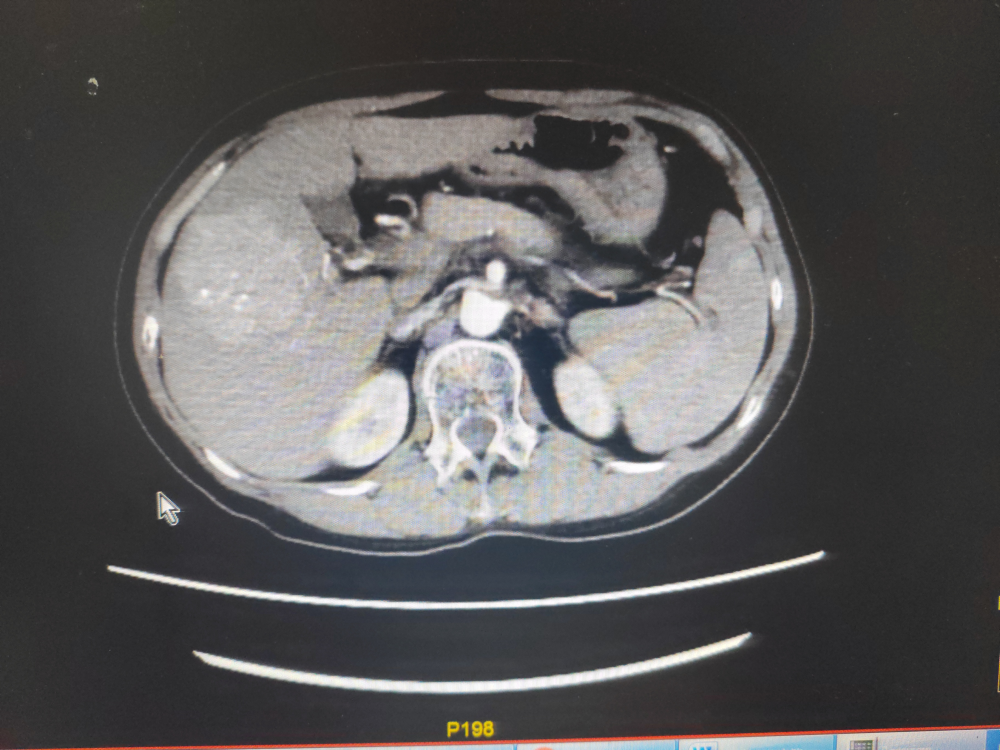

患者劉某,男,47歲,因腹痛於2022年1月17日在我院門診就(jiù)診,門診CT示:1、慢(màn)支肺氣腫及慢性炎症;2、右上(shàng)肺小結節,建議3-6個月(yuè)複查,3、掃及髒內異常密度灶建議必要時進一步檢查。當即轉往江西省腫瘤醫院就診,完善檢查,診斷為原發性肝癌,當時予以TACE術及卡瑞利珠單抗聯合多納菲尼靶向治療。2022年3月6日為行免疫治療前往我院內三(sān)科住院治療,完善檢查示:上腹部增強CT示:肝VI段及V段腫塊並碘(diǎn)油沉(chén)積,係介入治療術後改變,肝V段病(bìng)灶大部分存活,肝VI段病灶小(xiǎo)部分存活:肝I1 段小結節並(bìng)異常強化考慮小血管瘤:肝內多發(fā)微囊(náng)腫,肝門及腹(fù)膜後多(duō)發稍大(dà)淋巴結。甲胎蛋白(bái)異質體:322.82ng/ml個甲胎蛋白(bái):818.02ng/ml個甲胎蛋白異質體比率:40.09%完善術前檢查於2022 年3月10日在南昌(chāng)大學(xué)第(dì)一附屬(shǔ)醫院羅榮光副主任醫師指導下,內(nèi)三(sān)科肖緒銀副(fù)主任醫師、柯於鋒副主任醫師、盧軍主治醫師(shī)完成了我院首例經導管(guǎn)肝癌栓塞術,術後恢複良好,此後(hòu)患者定期行免(miǎn)疫治療。此後定期複查病情穩(wěn)定,2023年4月15日(rì)CT示:與2022年10月25日上腹部CT平掃(sǎo)及增(zēng)強比(bǐ)較:1、肝VI段及V段腫塊並碘油沉積,係介(jiè)入治療術後改變,腫塊大致相仿,未見明確強化,隨診(zhěn)複查(chá)。2、肝段小(xiǎo)結節(jiē)並異常強化,考慮小血管瘤肝內多發微囊腫:肝門及腹膜(mó)後多發稍大淋巴結;均較前片變化不(bú)著。3、脾前緣無明顯強化低密度灶,同前。4、右腎(shèn)微小結石。2023年4月16日(rì)甲(jiǎ)胎蛋(dàn)白:9.39ng/ml1療效評價大PR。

2022年3月7日上腹部增強CT

2023年4月15日上腹部增強CT